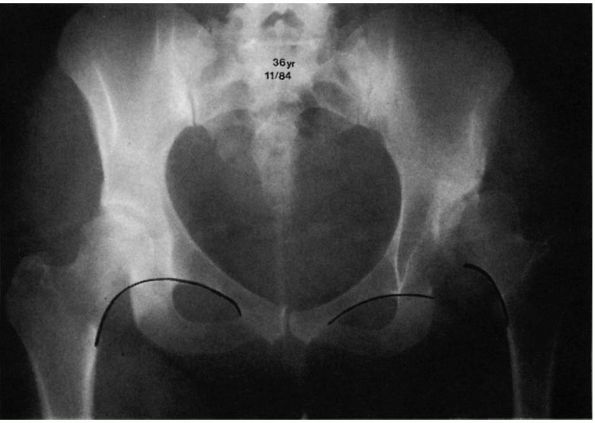

development stunted. The proximal femur is seen to lie laterally with

varying degrees of proximal migration compared with the ilium. The

Shenton line is disrupted. The acetabulum fails to develop, as

manifested by an increase in the slope of the acetabular roof (Figure 15-4).

![]() |

|

FIGURE 15-4.

Eleven-month-old boy with left congenital hip dysplasia. Note the delayed appearance of left femoral ossific nucleus, disruption of the Shenton line with proximal migration of the femur, and lack of development of the acetabulum manifested by an increased slope of the acetabular roof. |